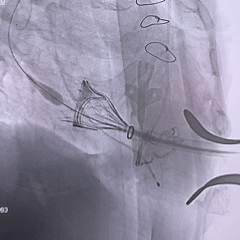

术中影像

瓣膜重新释放至全展开位,可见位置合适,流出端可见形态压缩

28mm球囊后扩,瓣膜形态明显改善

最终评估可见瓣膜形态、位置均理想